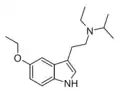

| Chemical structure | Short Name | Origin | Ring Substitution | RN1 | RN2 | Full Name | CAS Number |

|---|---|---|---|---|---|---|---|

| EiPT | artificial | H | CH2CH3 | CH(CH3)2 | N-Ethyl-N-isopropyltryptamine | 848130-11-0 |

| 5-MeO-DET | artificial | 5-OCH3 | CH2CH3 | CH2CH3 | 5-methoxy-N,N-diethyltryptamine | 2454-70-8 |

| 5-Ethoxy-DET | artificial | 5-OCH2CH3 | CH2CH3 | CH2CH3 | 5-ethoxy-N,N-diethyltryptamine | |

| 5-Ethoxy-EiPT | artificial | 5-OCH2CH3 | CH2CH3 | CH(CH3)2 | 5-ethoxy-N-ethyl-N-isopropyltryptamine | |